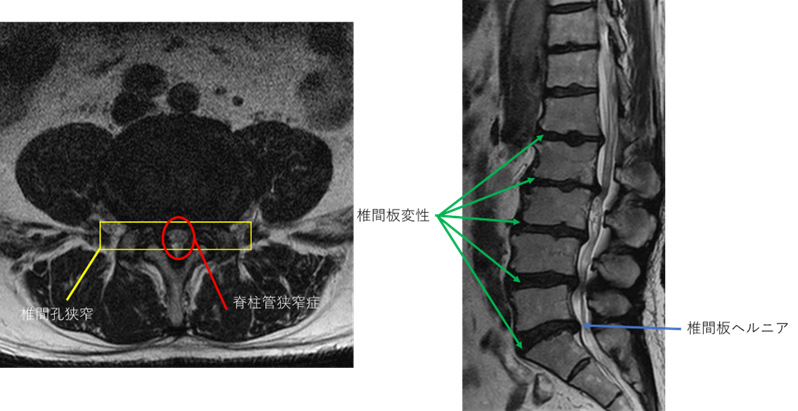

L1/2: 椎間板変性症

L2/3: 椎間板変性症、両椎間孔狭窄

L3/4: 椎間板変性症、両椎間孔狭窄

L4/5: 椎間板変性症、両椎間孔狭窄、脊柱管狭窄症

L5/S: 椎間板変性症、椎間板ヘルニア

以上の事が画像上認められます。

L1/2、2/3、3/4、4/5、5/S に

椎間板変性症、椎間孔狭窄、脊柱管狭窄症、椎間板ヘルニア を認め、主症状の原因の可能性が高い。